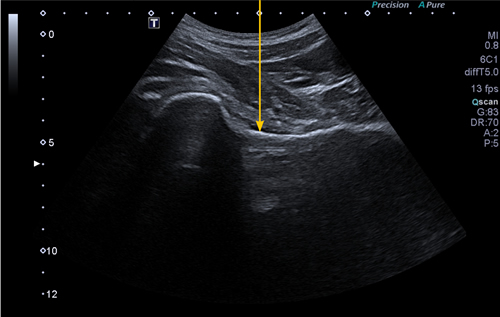

Figura 1